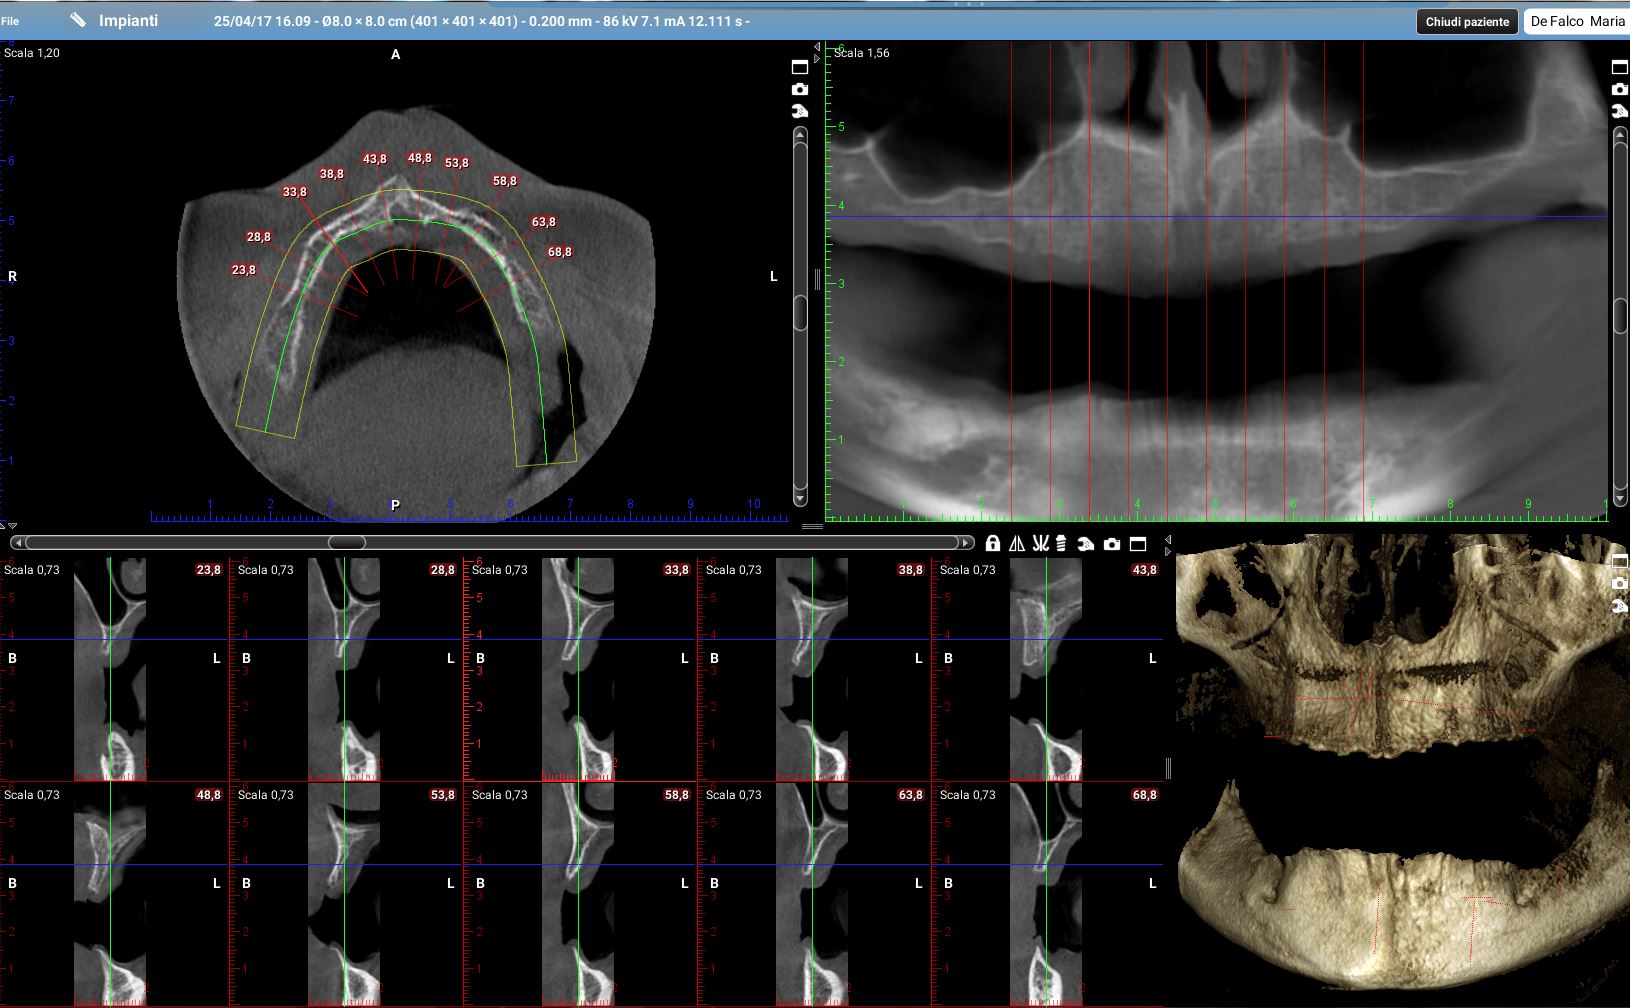

Durante l’ultimo corso di chirurgia Rocco (nome inventato) mi ha fatto vedere una cone-beam di un’arcata superiore; non ho la radiografia della sua paziente da usare come dato reale ma ti metto un mio caso concettualmente simile anche se un po’ più complesso.

Questa è la tomografia di una mia paziente.

Ora riprendiamo i tagli della cone-beam della mia paziente in corrispondenza delle zone dove dovrò posizionare i quattro impianti.

Impianto distale di destra:la cresta è larga molto meno di 4mm per tutta la sua estensione in altezza. E di lì l’impianto ci deve passare!

il programma di progettazione, che tra l’altro fornisce una bella area di sicurezza intorno al volume della fixture, dice “NON SI PUO”!

Impianto mesiale di destra:

se vogliamo ricercare uno spessore di cresta che superi i 4 mm dobbiamo andare a 5mm dal pavimento del naso. Io non farei un carico immediato full-arch su un impianto da 5mm!

Anche qui il programma di simulazione dice “NON SI PUO’”!

Sulla sinistra e pure peggio!